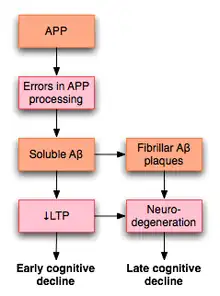

LTP has received much attention among those who study Alzheimer's disease (AD), a neurodegenerative disease that causes marked cognitive decline and dementia. Much of this deterioration occurs in association with degenerative changes in the hippocampus and other medial temporal lobe structures. Because of the hippocampus' well established role in LTP, some have suggested that the cognitive decline seen in individuals with AD may result from impaired LTP.

In a 2003 review of the literature, Rowan et al. proposed one model for how LTP might be affected in AD.[64] AD appears to result, at least in part, from misprocessing of amyloid precursor protein (APP). The result of this abnormal processing is the accumulation of fragments of this protein, called amyloid β (Aβ). Aβ exists in both soluble and fibrillar forms. Misprocessing of APP results in the accumulation of soluble Aβ that, according to Rowan's hypothesis, impairs hippocampal LTP and may lead to the cognitive decline seen early in AD.

AD may also impair LTP through mechanisms distinct from Aβ. For example, one study demonstrated that the enzyme PKMζ accumulates in neurofibrillary tangles, which are a pathologic marker of AD. PKMζ is an enzyme with critical importance in the maintenance of late LTP.[65]